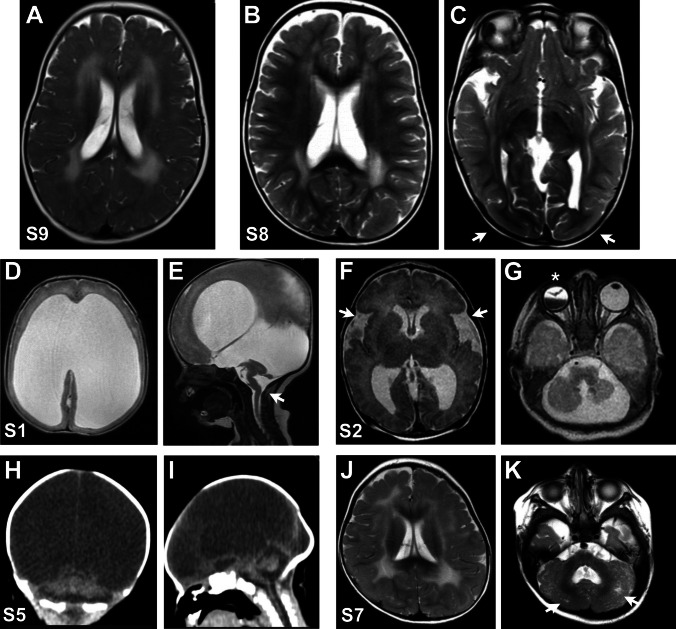

Congenital muscular dystrophies (CMDs) are a group of rare muscle disorders characterized by early onset hypotonia and motor developmental delay associated with brain malformations with or without eye anomalies in the most severe cases. In this study, we aimed to uncover the genetic basis of severe CMD in Egypt and to determine the efficacy of whole exome sequencing (WES)-based genetic diagnosis in this population. We recruited twelve individuals from eleven families with a clinical diagnosis of CMD with brain malformations that fell into two groups: seven patients with suspected dystroglycanopathy and five patients with suspected merosin-deficient CMD. WES was analyzed by variant filtering using multiple approaches including splicing and copy number variant (CNV) analysis. We identified likely pathogenic variants in FKRP in two cases and variants in POMT1, POMK, and B3GALNT2 in three individuals. All individuals with merosin-deficient CMD had truncating variants in LAMA2. Further analysis in one of the two unsolved cases showed a homozygous protein-truncating variant in Feline Leukemia Virus subgroup C Receptor 1 (FLVCR1). FLVCR1 loss of function has never been previously reported. Yet, loss of function of its paralog, FLVCR2, causes lethal hydranencephaly-hydrocephaly syndrome (Fowler Syndrome) which should be considered in the differential diagnosis for dystroglycanopathy. Overall, we reached a diagnostic rate of 86% (6/7) for dystroglycanopathies and 100% (5/5) for merosinopathy. In conclusion, our results provide further evidence that WES is an important diagnostic method in CMD in developing countries to improve the diagnostic rate, management plan, and genetic counseling for these disorders.